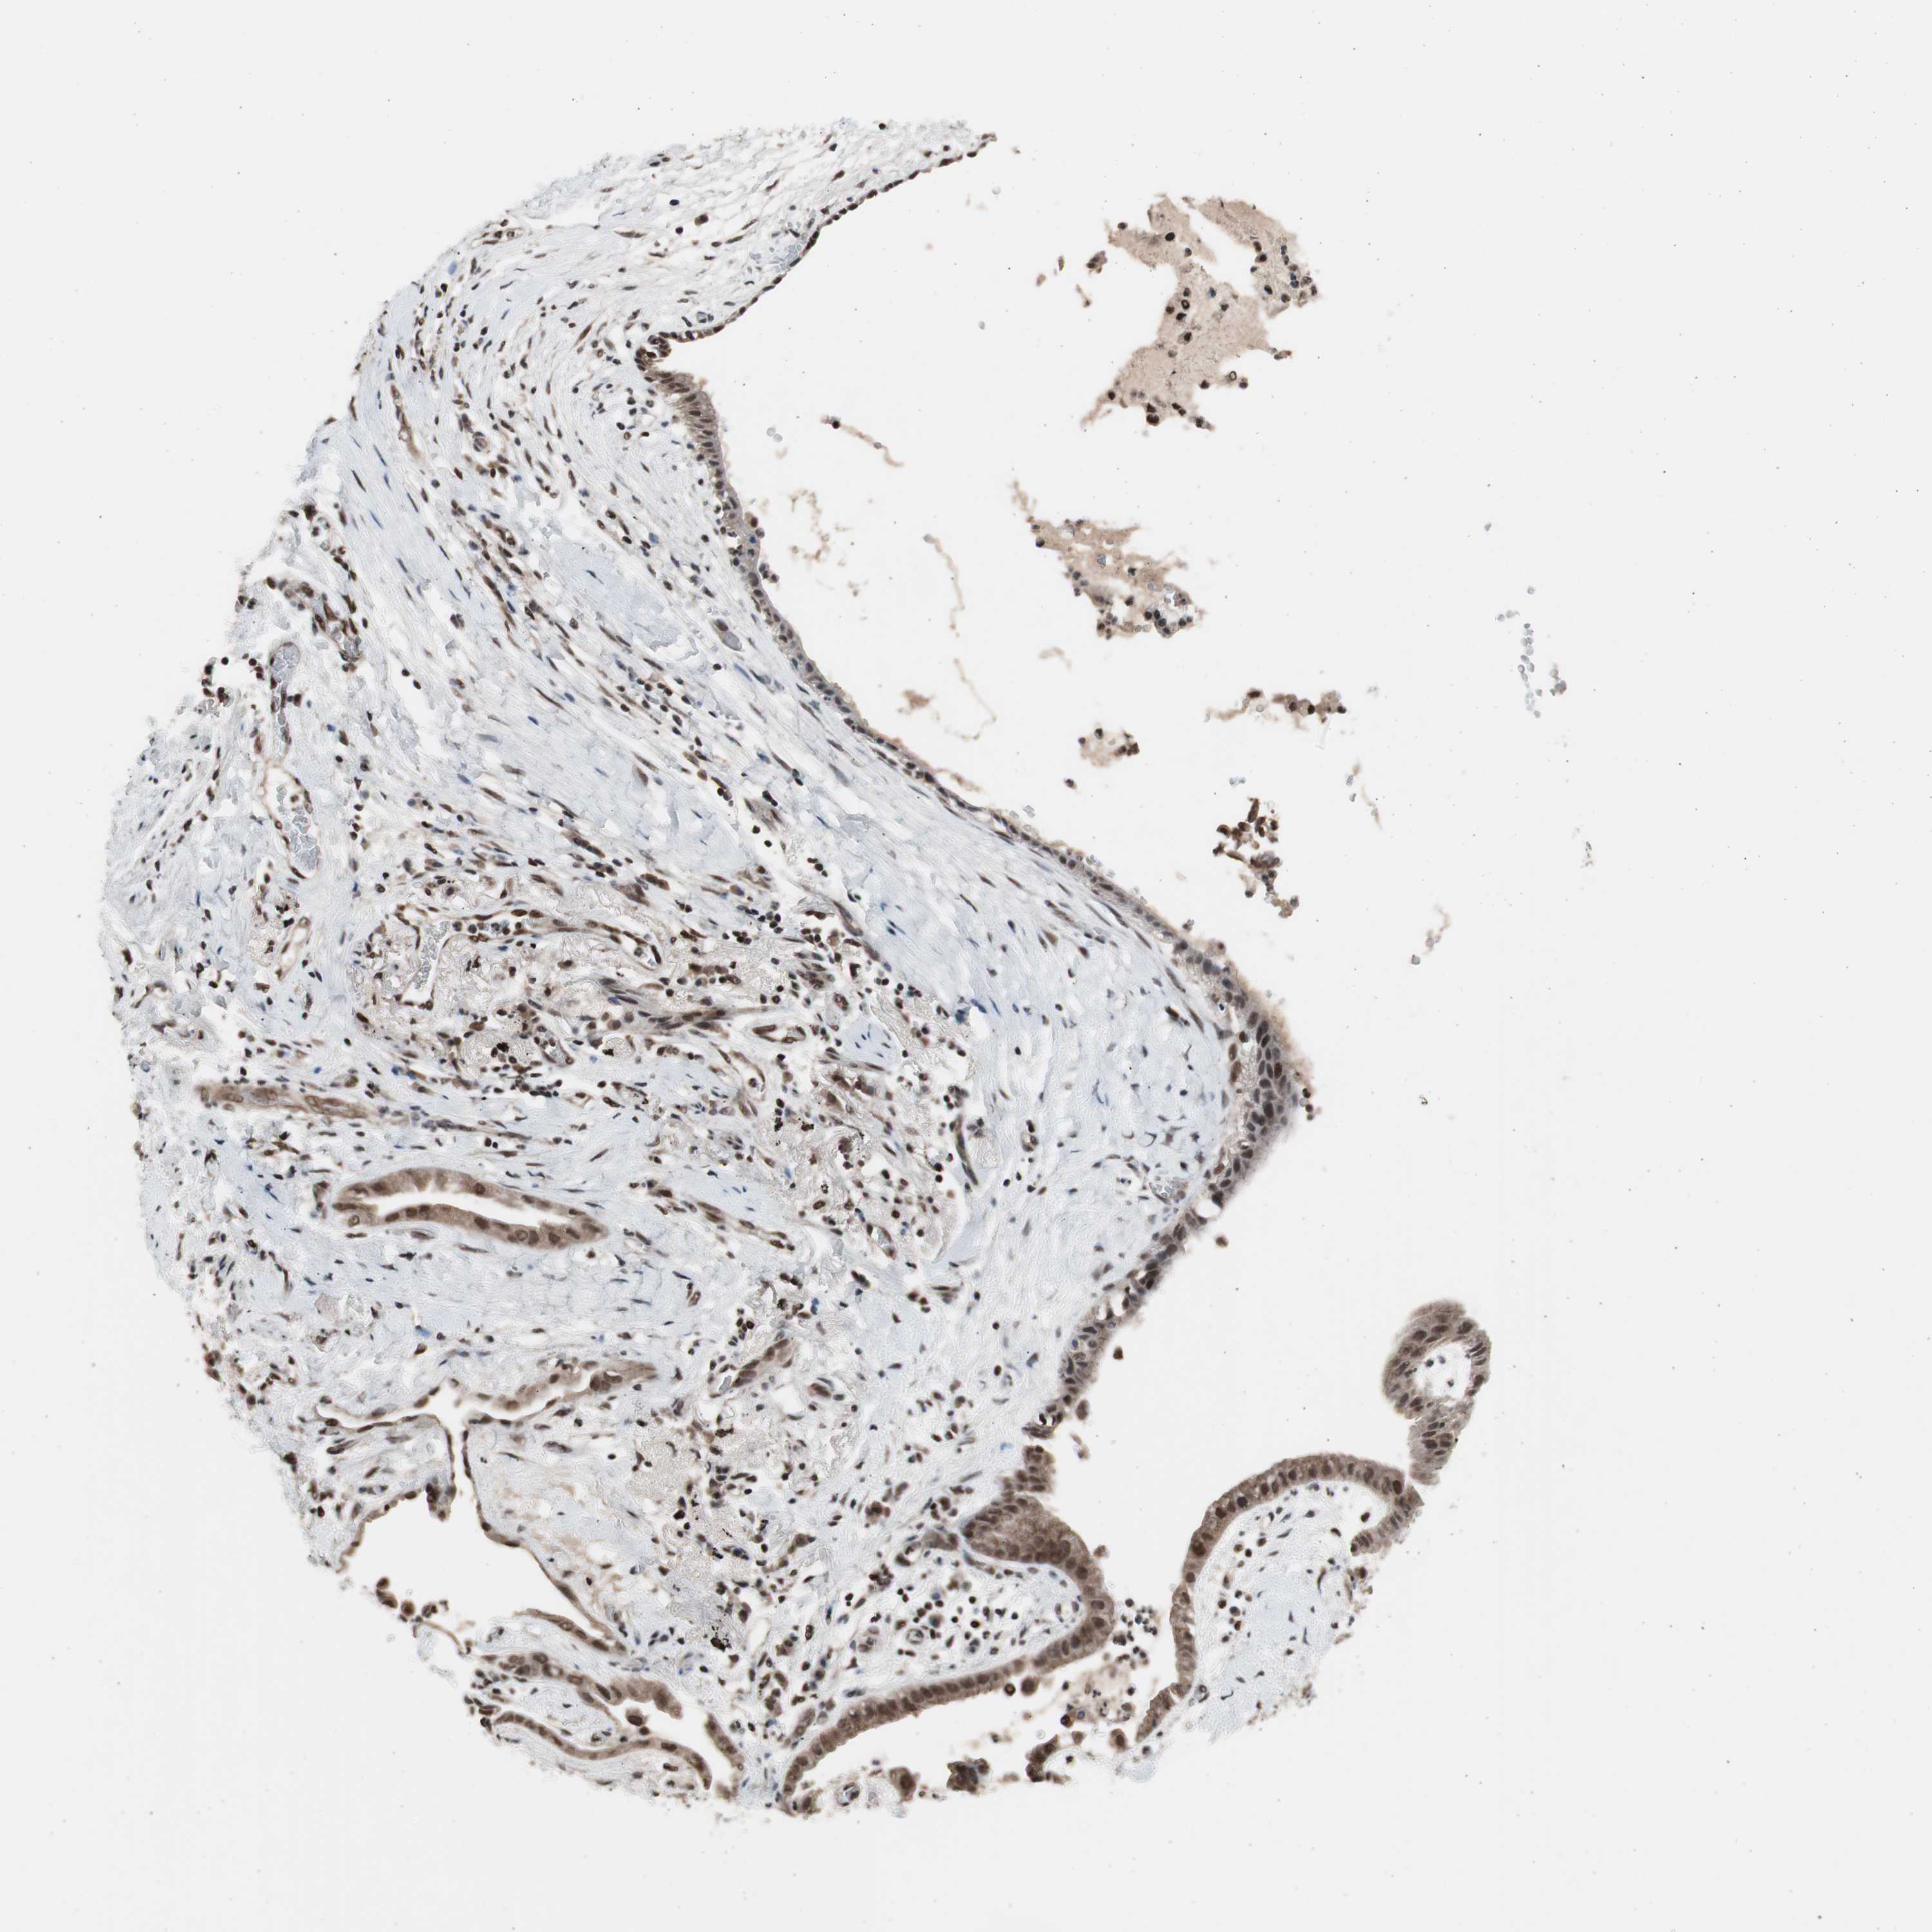

CANCER LUNG CANCER Show tissue menu